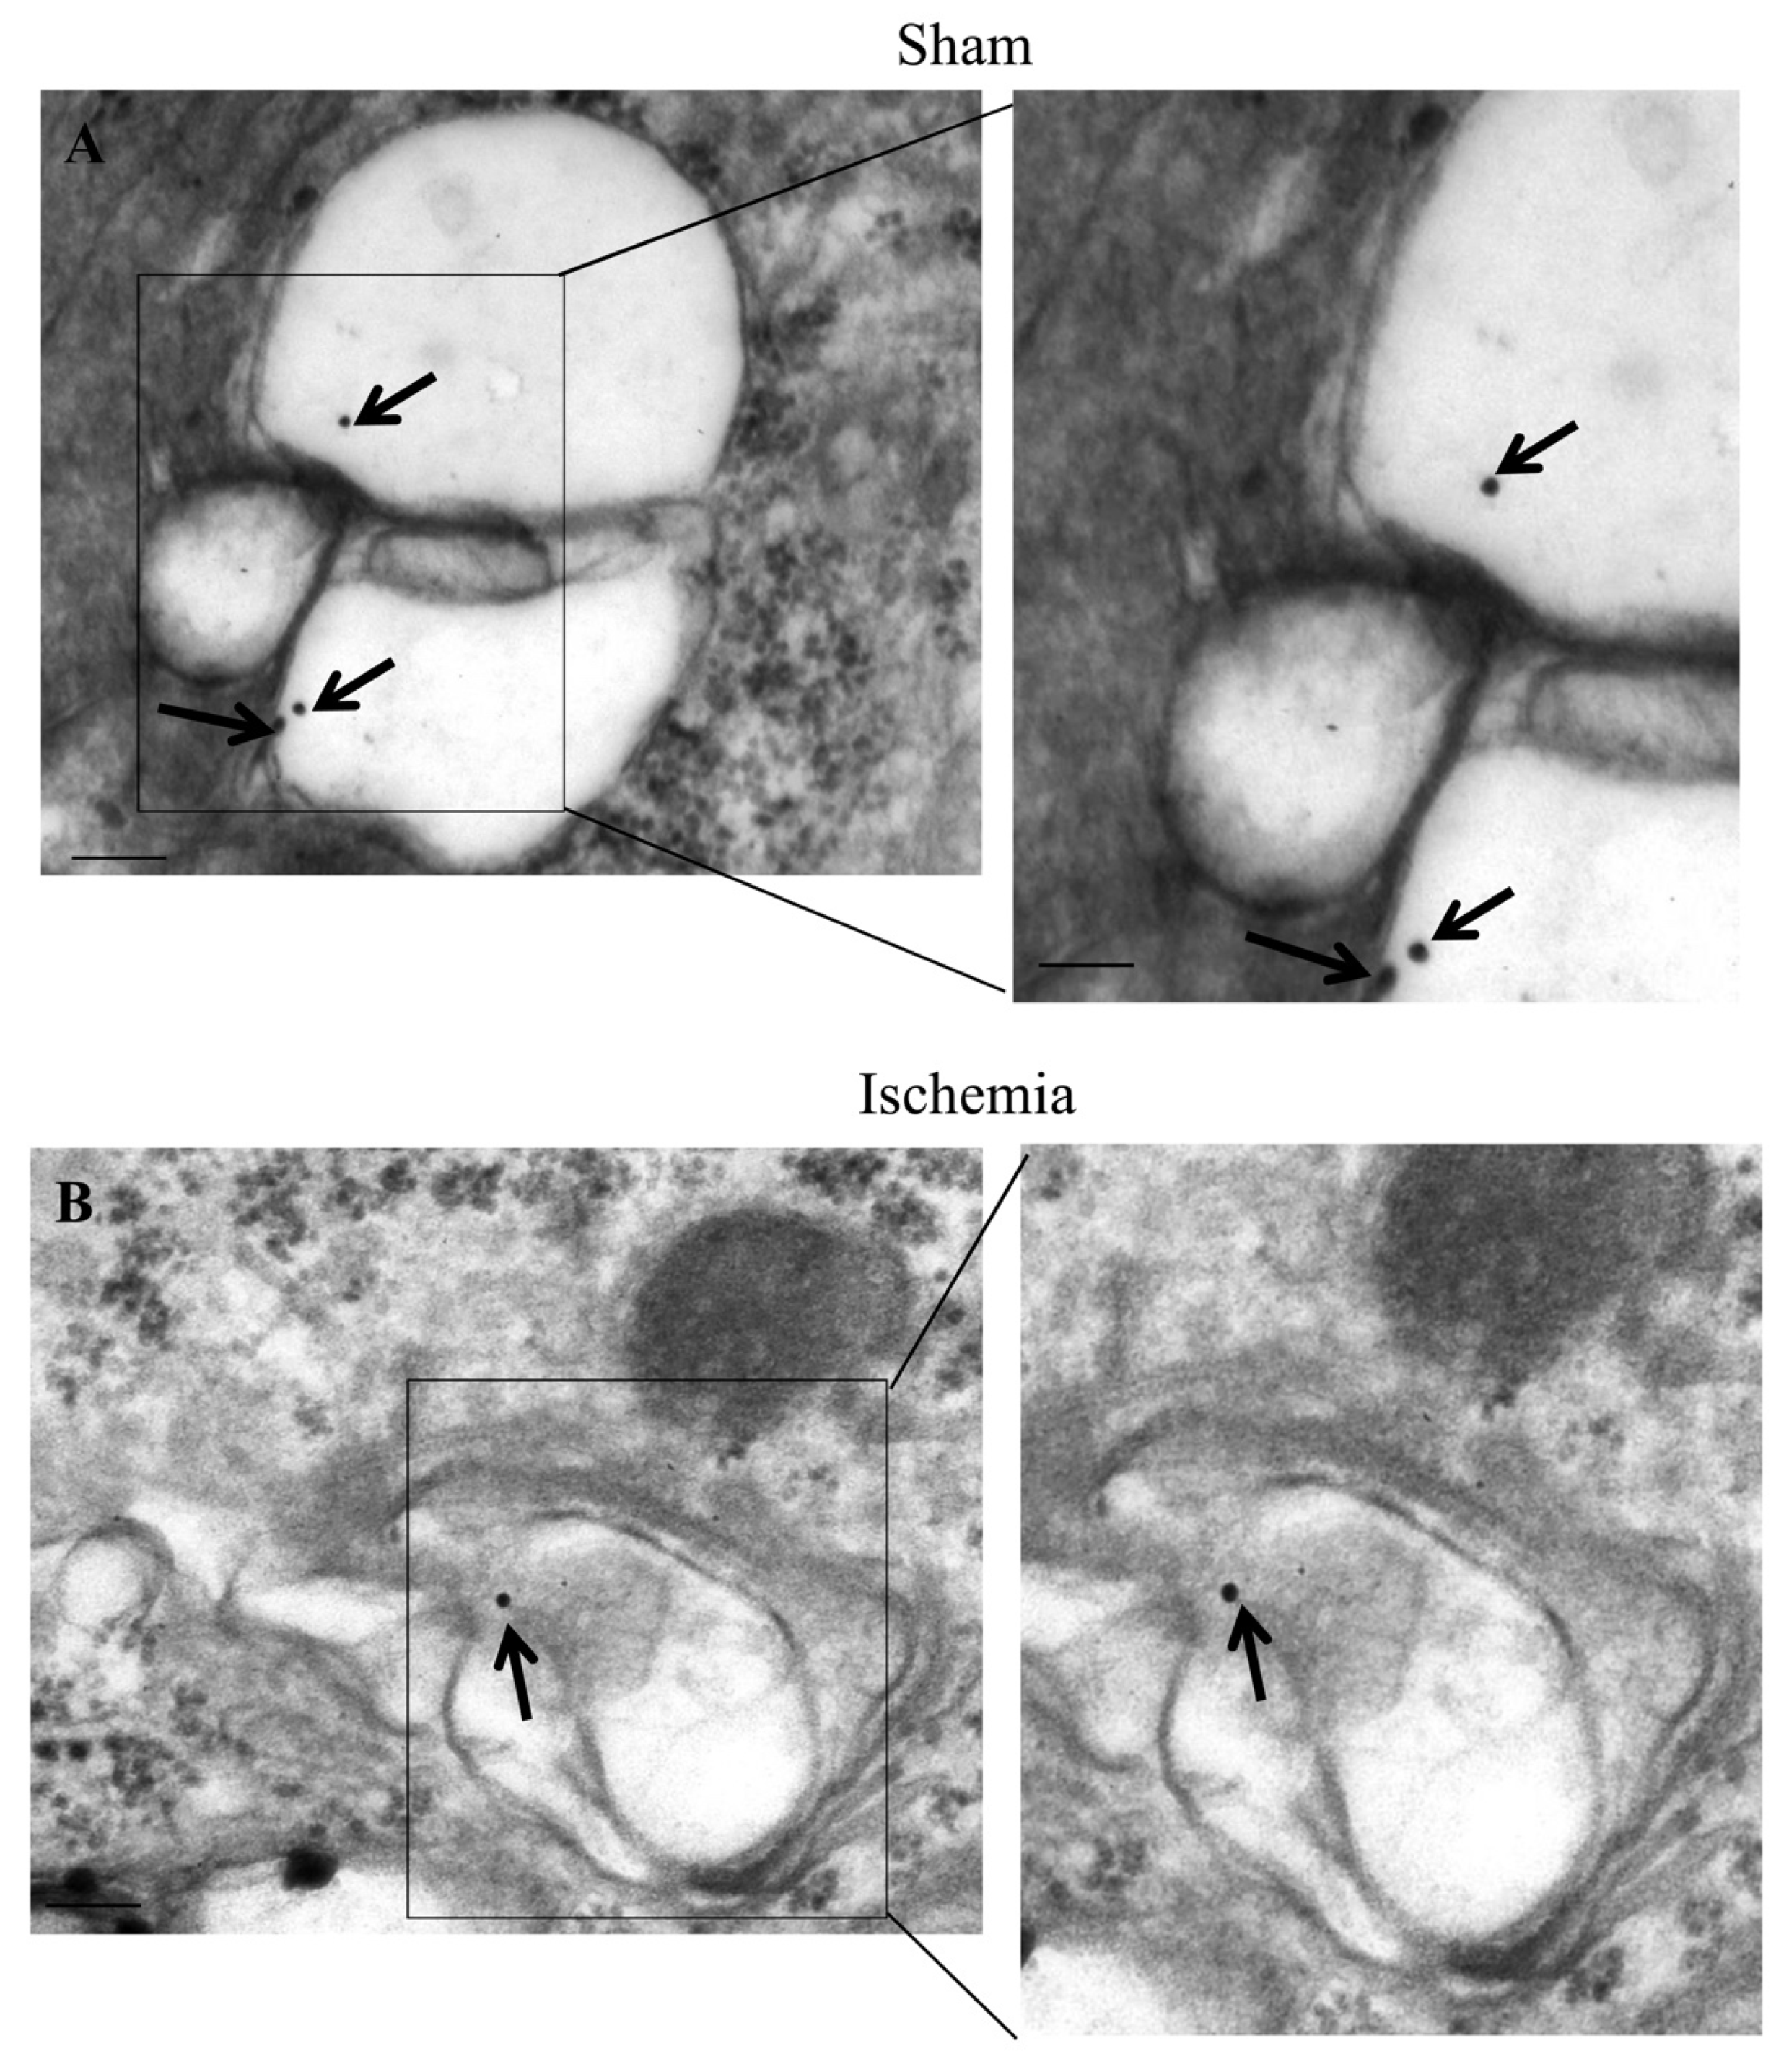

2.6. The Amount and Compartmentalization of LC3 within Area Penumbra

2.7. The Amount and Compartmentalization of P20S within Area Penumbra